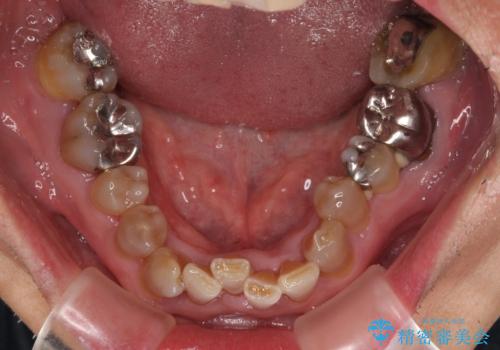

上下ともに前歯のセラミッククラウンによる補綴治療を希望されていましたが、下顎前歯は叢生が強いため、補綴治療前に部分矯正を行って歯列を整えた上で、補綴治療を行うこととしました。

臼歯部には歯周ポケットのある箇所が散見されましたが、まずは前歯を治療したいとのことで、治療を進めました。

ディープバイトにより臼歯部に負担のかかる咬合であったので、補綴治療後には、矯正治療の後戻り防止もかねて、睡眠時にマウスピースを装着するように指示しました。